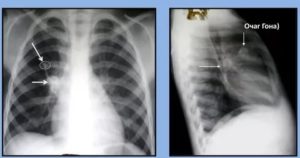

Очаг Гона на рентгенограмме выглядит как затемненное образование с резкими очертаниями. Излюбленным местом локализации признаются нижние и средние зоны органа. Легочный рисунок при этом редко изменен, корень практически не расширен.

При рентгенологических исследованиях очаг Гона представляет собой затемнение овальной (реже округлой) формы с резкими очертаниями, размерами до 5 мм. Образования могут быть единичными и множественными. Излюбленная их локализация – нижние и средние отделы легких. Иногда контуры очага могут быть неровные. Легочный рисунок неизменен, корень не расширен.

На разных этапах петрификации (обызвествления) очага Гона изменяется, структура его может быть:

- гомогенной (однородной),

- негомогенной: имеет зернистое или дольчатое строение, неровные границы.